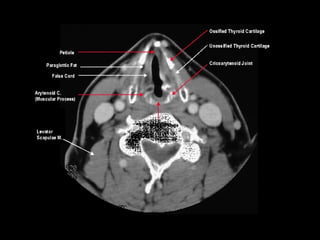

Radiographers use medical imaging equipment like X-rays and MRIs to produce images of patients' internal structures and organs. They are responsible for positioning patients, operating scanning machines, and ensuring quality images. Radiographers must have strong attention to detail, excellent communication skills, and the ability to work well under pressure to accurately capture anatomical features and diagnose any abnormalities.